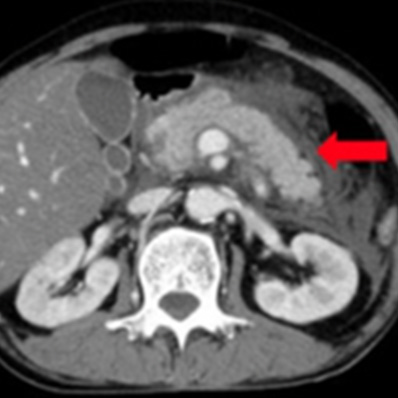

腹部大動脈瘤破裂

外傷性脾損傷

外傷による腹腔内出血